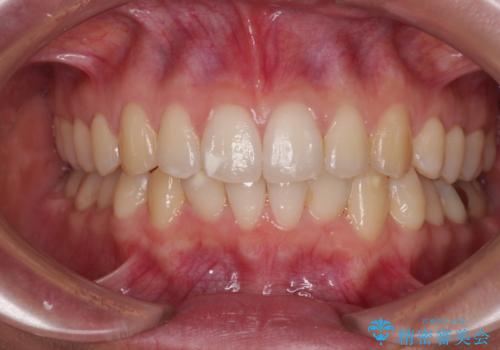

[ 歯を抜かないマウスピース矯正 ] 不揃いの目立つ前歯をきれいにしたい

担当医 大元洋佑

![[ 歯を抜かないマウスピース矯正 ] 不揃いの目立つ前歯をきれいにしたいの症例 治療後](https://seimitsushinbi.jp/wp/wp-content/uploads/2023/08/IMG_9796-500x350.jpg?v=1691028808)